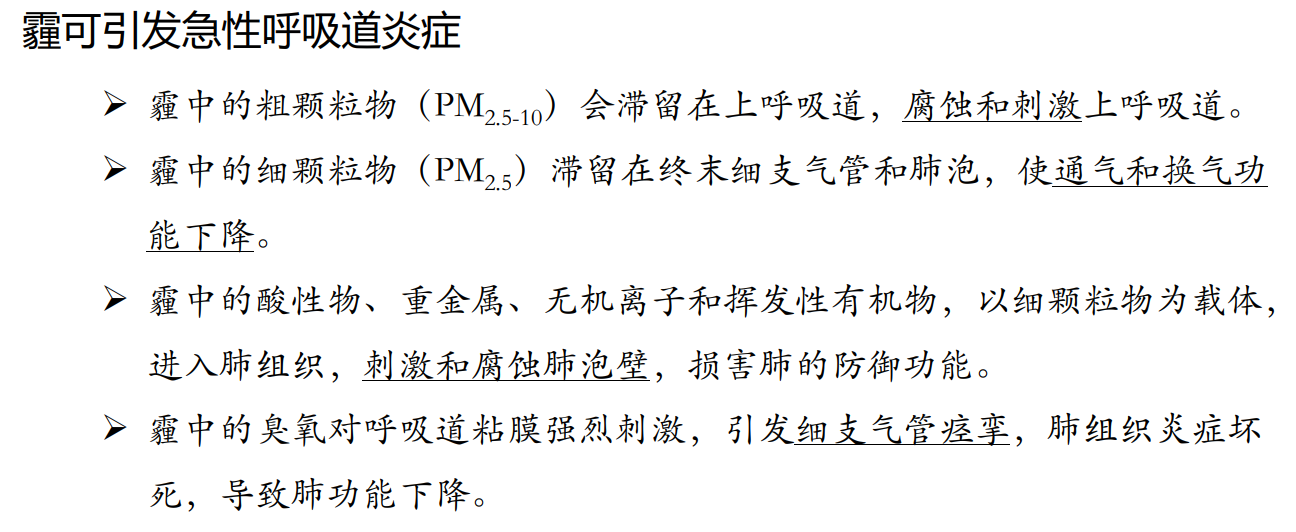

霾与肺疾患

哮喘

支气管或肺部的疾病所引起,称为肺源性哮喘。

1)支气管哮喘:是一种过敏性疾病,来去较快;哮喘停止后如同正常人一样。

2)喘息性支气管炎:病人除有慢性支气管炎的症状:长期咳嗽、咳痰,在呼吸道感染时加重。

3)支气管肺癌:当癌瘤堵塞大支气管时,也可引起喘息。病人呼气、吸气时均感到困难。

哮喘虽然不能彻底治愈,但完全可以控制,减少发作。